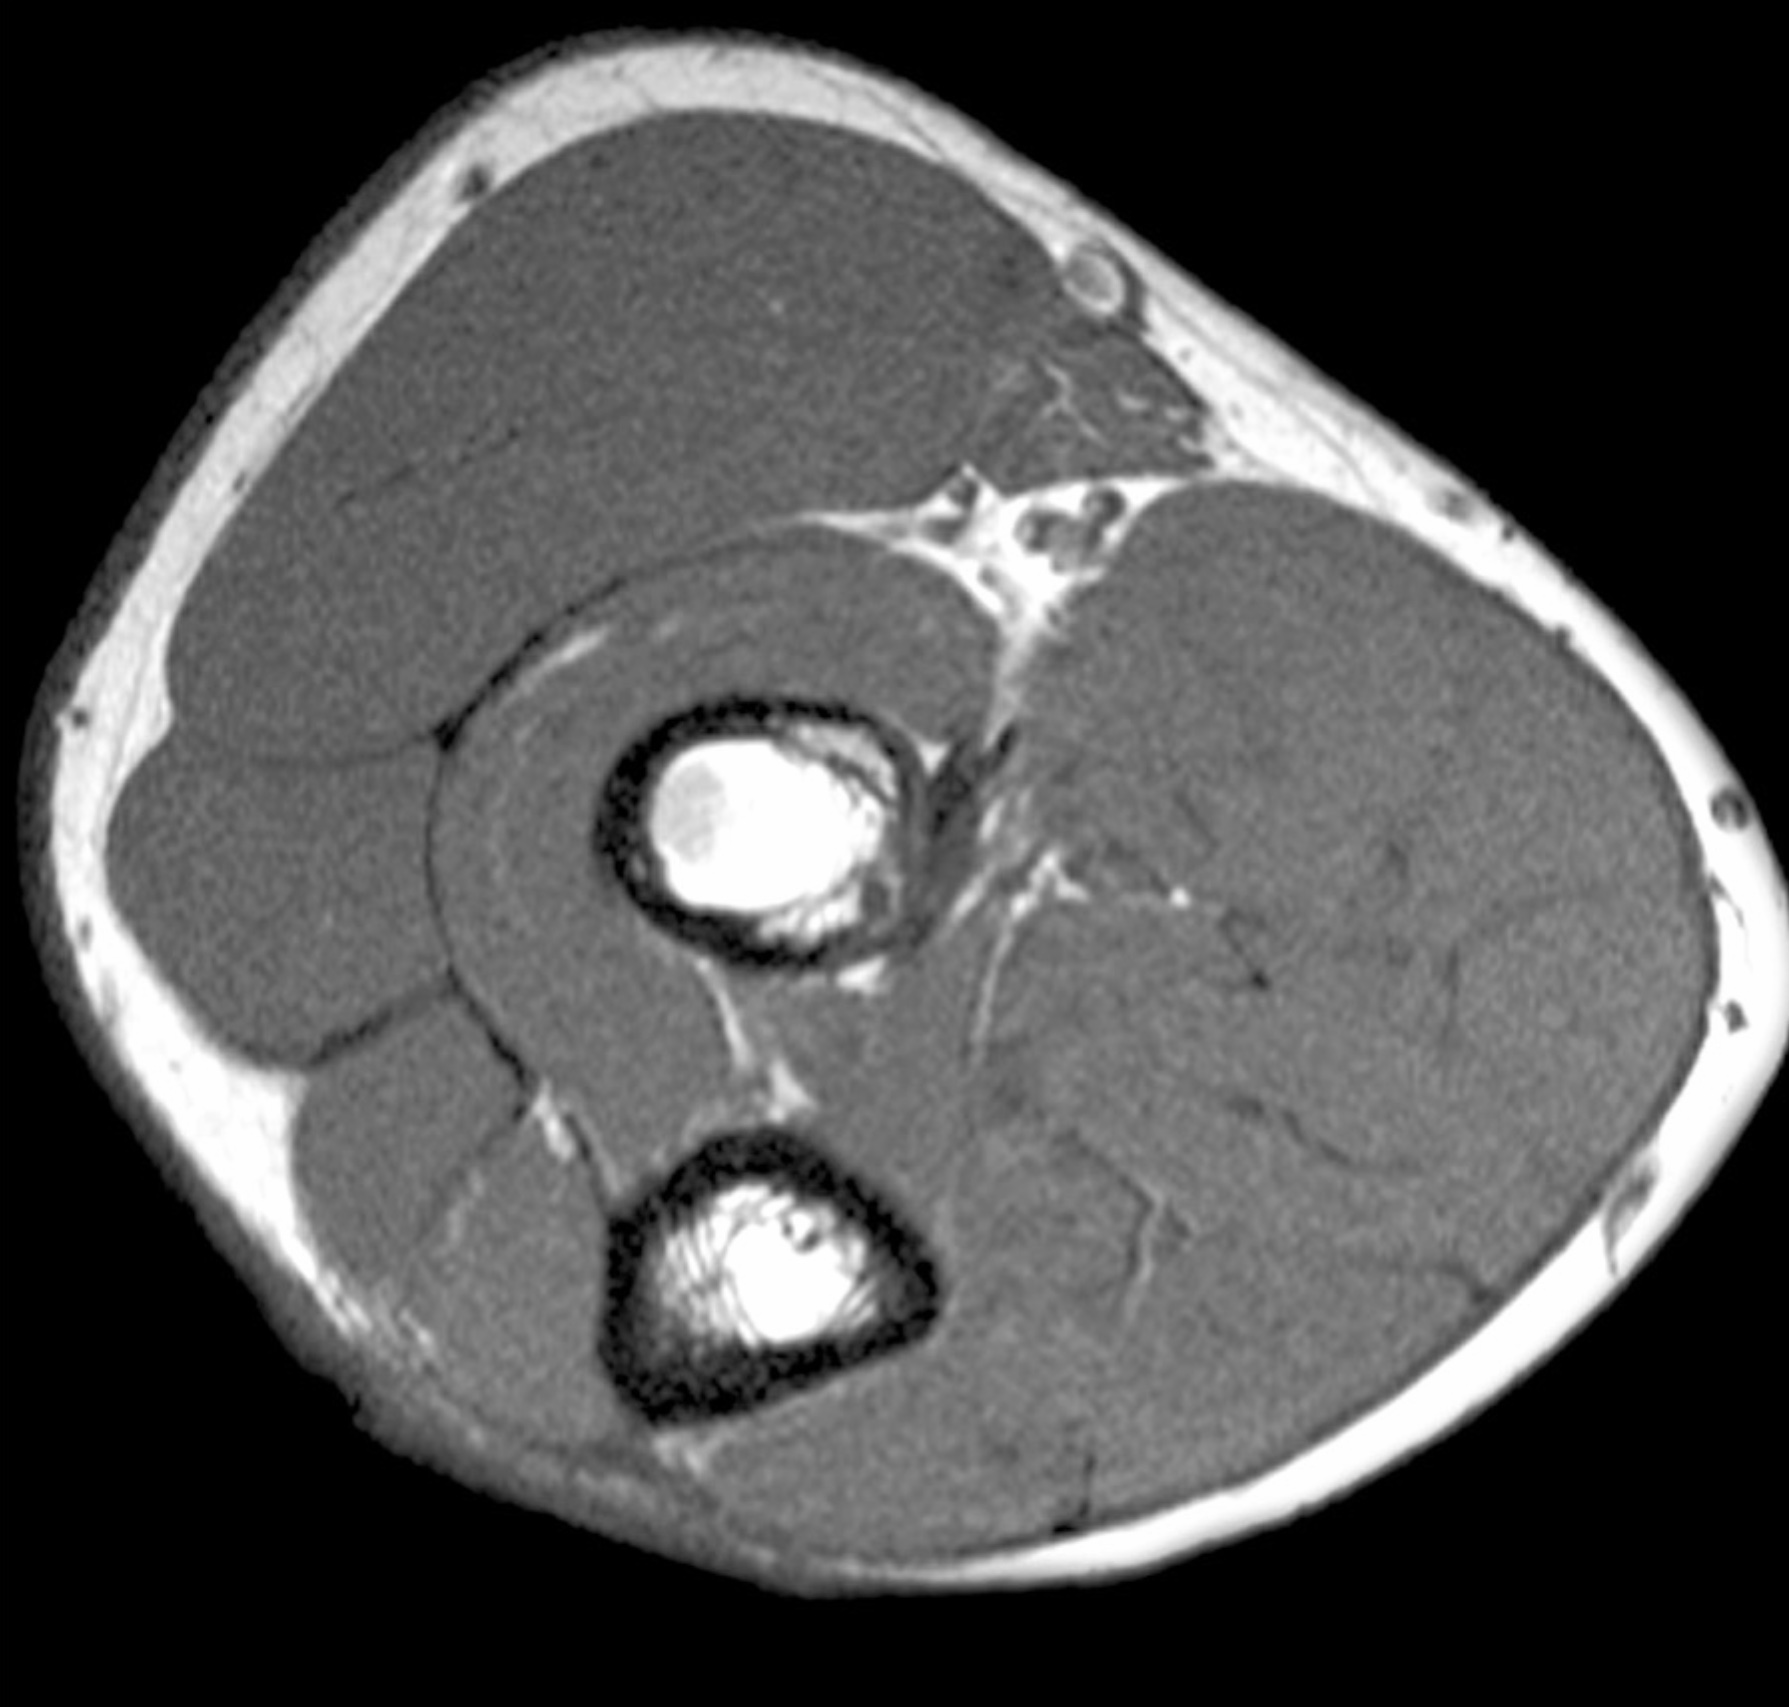

1. The biceps brachii muscle is the most powerful supinator. Discuss the anatomy of the anterior compartment of the arm, including boundaries, contents, musculature, vascular supply, innervation, lymphatics and relationships.